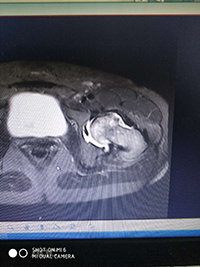

术前再次确认股骨头坏死区域: